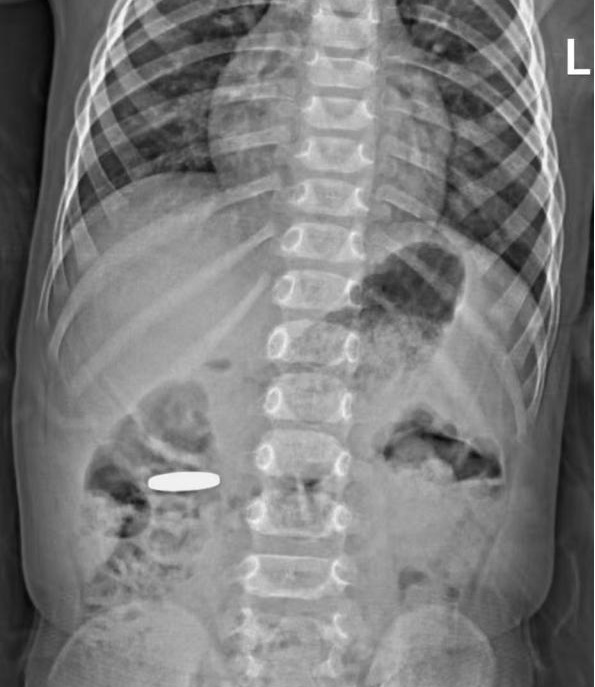

急诊的X光检查很快给出了明确结果:在童童上腹部区域,清晰显示出一个典型的椭圆形金属密度影,正是那枚“失踪”的硬币。万幸的是,这枚硬币形状规则、边缘光滑,没有尖锐凸起,大大降低了对肠道黏膜的划伤风险。医生结合童童当时无腹痛、呕吐等不适的状态判断,硬币大概率能随着肠道蠕动自行排出体外,无需立即手术干预。

而相比误吞硬币,磁力珠(巴克球)对孩子肠道的伤害更为严重。3岁男孩航航(化名)趁家长不注意,偷偷将玩耍的数颗磁力珠(巴克球)塞进了嘴里。影像科的X光片清晰显示出超过10颗小球状高密度影,它们没有分散在肠道各处,反而紧紧吸附在一起,形成了明显的“串珠样”。